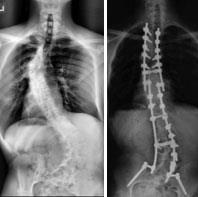

Spinal fusion. To treat severe scoliosis caused by NF1, the doctor may recommend surgery.

The operation for scoliosis is a spinal fusion. This is essentially a welding process. The basic idea is to realign and fuse together the curved vertebrae so that they heal into a single, solid bone. Implants made up of screws, rods, hooks, or wires will keep the bones in place while the fusion heals.

Treatment with spinal fusion

(Left) This X-ray shows a severe scoliosis curve in a 14-year-old boy with NF1. (Right) The same patient's spine after spinal fusion surgery.

Reproduced with permission from Feldman DS, Jordan C, Fonseca L: Orthopaedic manifestations of neurofibromatosis type 1. J Am Acad Orthop Surg 2010; 18:346-357.